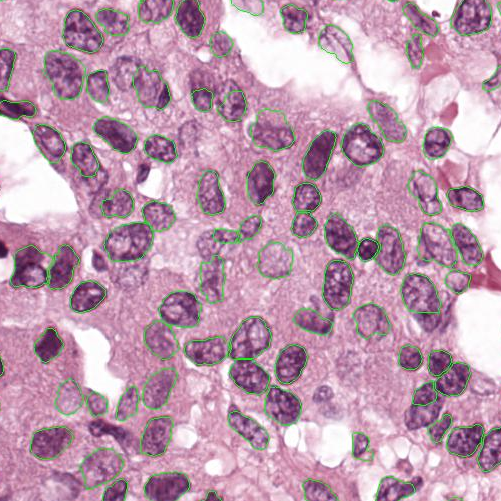

As an essential part of digital pathology, histopathology image analysis is playing increasingly important role in cancer diagnosis, which can provide direct and reliable evidence to diagnose the grade and type of cancer. This paper deals with nuclei segmentation, an important step in histopathological image analysis. The purpose of nuclei semgentation is not only counting the number of nuclei but also obtaining the detailed information of each nucleus. So unlike nuclei detection, here the outputs are the contour of each nucleus instead of only the position of their central points. Hence we can exactly extract each nucleus from the image and make it available for further analysis. For example, the features of the individual nucleus and the distribution of nuclei clusters can be used to grade and classify status of breast cancers [3, 4]. Because of appearance variation such as color, shape, and texture, nuclei segmentation from histopathological images could be very challenging, as illustrated in Fig.1, in which it is very challenging even for human to recognize and segment all nuclei within the images. Fig.1(a) and Fig.1(b) illustrate two histopathological images from different organs. Fig.1(c) and Fig.1(d) are two histopathological images from same organ but have different cancer grade.

Figure 6 shows how our method segments the nuclei step by step. The color variety is well controlled by the color normalization procedure. The prediction result shows clear nuclear areas and nucleus boundaries. In the final segmentation result and ground truth image, each nucleus is represented by a different color.